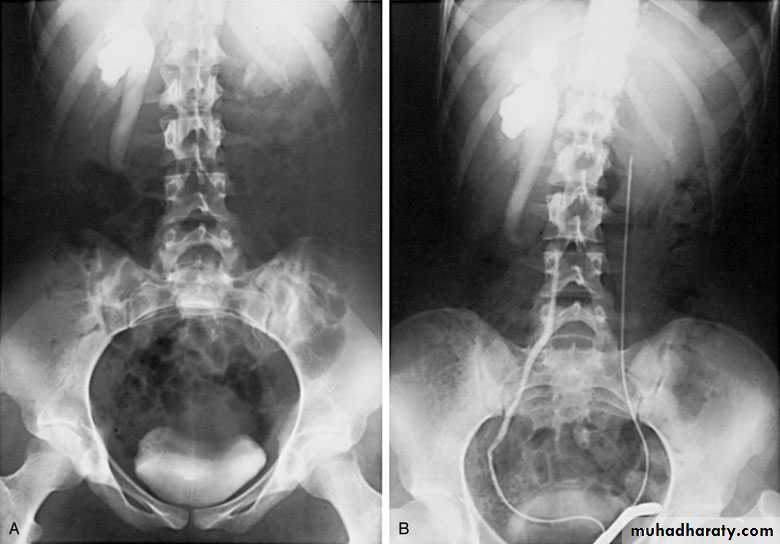

Ureteropelvic Junction (UPJ)(PUJ) Obstruction (stenosis)

The most common cause of significant dilation of the collecting system in the fetal kidney

Boys > Girls

Left-sided lesions predominate

15% bilateral

DIAGNOSIS

U/S: hydronephrosis

IVU: diagnostic , hydronephrosis with

fixed stenotic segment or complete

obstruction

CT scan: hydronephrosis that ends

abruptly

Bilateral PUJO